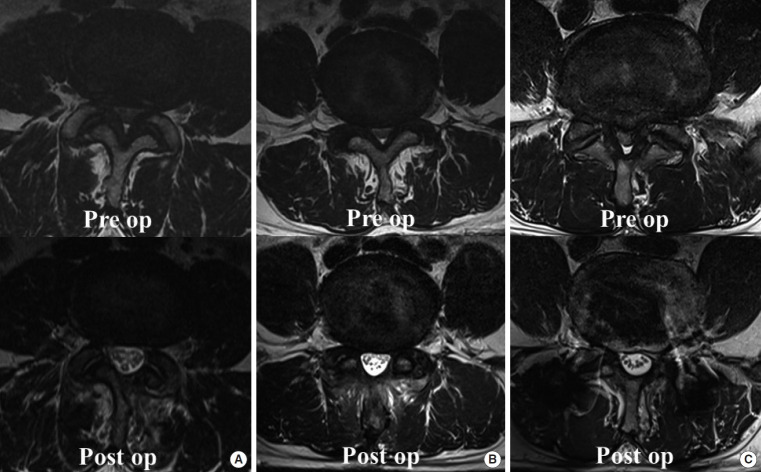

Methods: This retrospective study included 86 patients, divided into ULBD-UBE (n=34), STL (n=24), and MIS-TLIF (n=28) groups. We evaluated demographics and perioperative factors and assessed clinical outcomes using the visual analogue scale (VAS), Oswestry Disability Index (ODI), and neurogenic intermittent claudication (NIC). Radiological parameters assessed included lumbar lordosis, L4S1 Cobb angle (L4S1), T12S1 Cobb angle (T12S1), increased cross-sectional dural area (CSA), dynamic angulation (DA), dynamic slip (DS), and development of postoperative instability.

Results: The ULBD-UBE group showed a significantly shorter hospital stay duration and operation time and reduced blood loss than the other groups (p<0.001). ULBD-UBE group showed a trend towards greater VAS and ODI improvement at 1 month and postoperative NIC symptom relief. Radiologically, MIS-TLIF group exhibited lower postoperative DA and DS (p<0.001), indicating higher postoperative stability. Postoperative instability was lower in the ULBD-UBE group (2.9%) than in the STL group (16.7%) and similar to the MIS-TLIF group (0.0%) (p=0.028). The CSA was highest in the MIS-TLIF group (295.5%) compared to that in the other groups (ULBD-UBE, 216.3%; STL, 245.2%) (p<0.001).